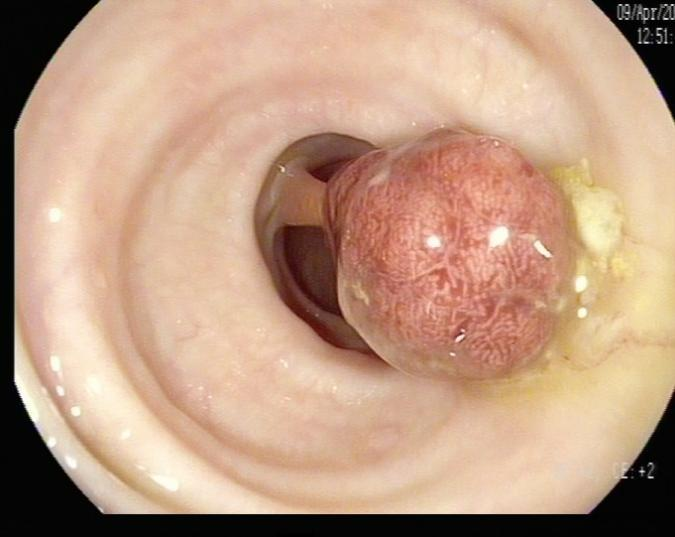

陈先生(44岁,乙状结肠息肉,图2)

肠镜一照,息肉现形!形态各异的大肠息肉,离癌有多远?(图2)

图2

病理诊断:(乙状结肠)管状腺瘤,局灶癌变-黏膜内癌(腺癌),脉管未见癌栓,蒂未见累及。

解读:这是从腺瘤发展成癌的典型案例。“局灶癌变”指息肉中只有一小部分区域发生了真正的癌变。“黏膜内癌”指癌细胞仍局限于黏膜层内,尚未穿透黏膜肌层向更深层浸润。脉管无癌栓、蒂部未累及是非常积极的信号,表明癌细胞尚未通过血管/淋巴管扩散,也未侵犯息肉蒂部。此时完整切除息肉,很大可能达到根治效果。距离进展期癌:非常近,但尚属极早期,原位癌/粘膜内癌。